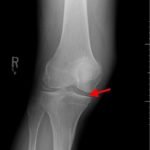

Radiographs of the knee showed multiple radio-dense lines paralleling the articular surface (see red arrows) consistent with calcium pyrophosphate crystal deposition within the joint often seen in calcium pyrophosphate disease (CPPD) also known as pseudogout.

Patients commonly present to the emergency department with non-traumatic joint pain. Arthrocentesis is an important diagnostic tool to evaluate for septic arthritis, gout, or pseudogout. Arthrocentesis can demonstrate crystals or abnormal cell count, gram stain, and culture.[1] In the evaluation of joint pain, plain films are usually obtained to evaluate for fracture, dislocation, effusion, or secondary signs of infection. In this case the classic x-ray supported the diagnosis of CPPD.2 The patient was found to have positively birefringent rhomboid shaped crystals consistent with pseudogout on arthrocentesis. Gram stain and culture were both negative. The patient was discharged with NSAIDs and had significant improvement in symptoms upon follow up with primary care physician in 3 days.